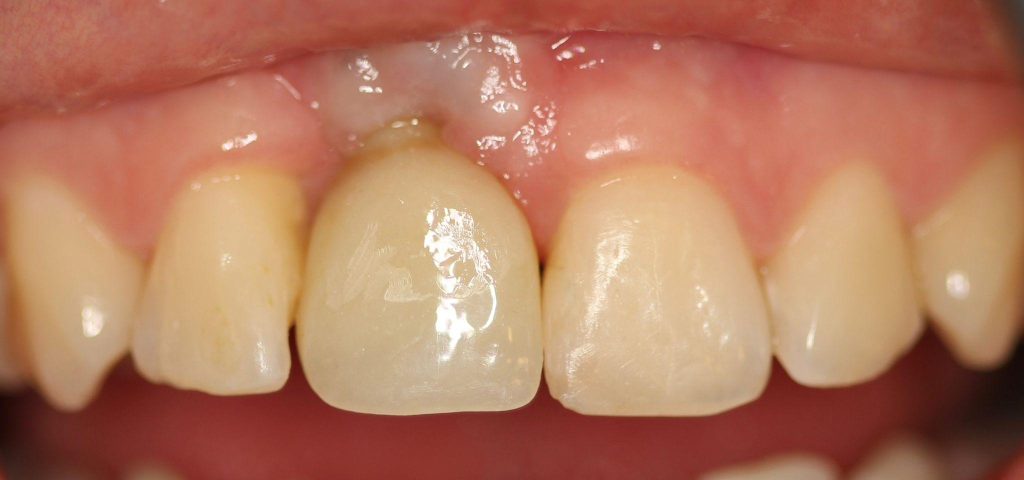

Aby osiągnąć taki efekt, musieliśmy przeprowadzić ekstrakcję złamanej górnej jedynki i w jej miejsce jednoczasowo wszczepić implant, a następnie na pozostałe zęby wykonać licówki i korony pełnoceramiczne w najjaśniejszym odcieniu.

Dobrze przeprowadzony zabieg implantacji natychmiastowej daje efekty jak na pozostałych zdjęciach! Na każdym etapie leczenia mamy pełną kontrolę nad wszystkimi aspektami przyszłej odbudowy protetycznej – można powiedzieć, że zachowujemy to, co najtrudneijsze do odtworzenia, czyli kształt dziąseł.

Cytując Michała Mokijewskiego: „Pacjent przychodzi po idealny ząb, a nie po implant”.

Tylko implantacja natychmiastowa pozwala nam uzyskać taki efekt w zaledwie 3 wizyty.